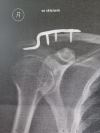

Utrhnul jsem si vazy v rameni dominantní ruky po pádu přes řidítka, původně diagnostikováno na Tossy II. – III., po kontrolním rentgenu jasná Tossy III. určenná k operaci.

- doporučuju si ofotit nebo vyžádat rentgenové snímky, já zatím fotil monitory, co mi doktoři ukázali, ale prej to dávaj i na jiná média typu CéDéčko a tak (v čem to v dnešní době přehraješ, to je už druhá otázka :-)

- pokud půjdete na operaci, nedoufejte v nějakou laparoskopii, je potřeba pečlivě prozkoumat co a kde se utrhnulo, na rentgenu to nidko přesně nepozná a vidět jsou jen kosti jak nejsou tam, kde mají být (ostatně jizvy z „boje“ prej chlapa ctí)